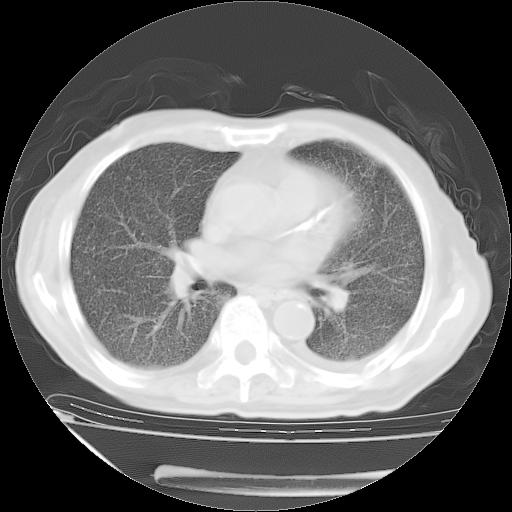

甲强龙80mg/日+抗结核治疗(异烟肼+利福霉素+乙胺丁醇)10天。复查肺部CT。

治疗10天肺部CT